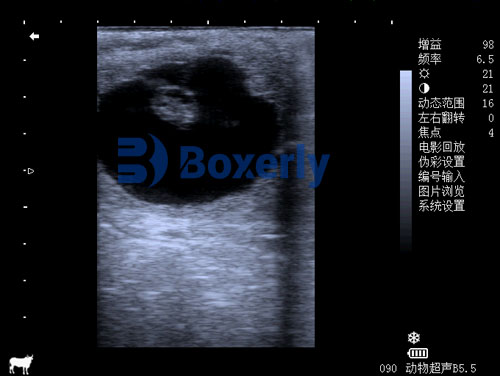

Transrectal B-mode Ultrasound

This is the standard method for early pregnancy diagnosis in mares. It provides real-time black-and-white imaging and allows veterinarians to examine the uterus, ovaries, and embryo in great detail.

Between days 21–25, the embryo proper becomes visible as a small structure inside the vesicle. By day 25, a flickering heartbeat can often be seen using B-mode ultrasound, confirming a viable pregnancy.

Indicator of health: Presence of heartbeat is the most reliable sign of fetal viability. A non-pulsating embryo or reduced heart rate may indicate stress or early embryonic death.